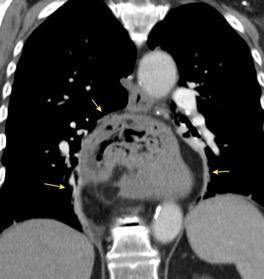

T. mixto de células germinales del testículo izquierdo

Nódulos pulmonares múltiples. (flechas verdes). Masas paratraqueales. (flechas amarillas). Dudoso ensanchamiento retrocrural (flechas negras). sigue….

Ttawfik A et al. Trans-diaphragmatic Pathologies: Anatomical Background and Spread of Disease on cross-sectional Imaging. Current Problems in Diagnostic Radiology. 2021.

T. mixto de células germinales del testículo

izquierdo Metástasis pulmonares. (flechas verdes). Ganglios paratraqueales. (flechas amarillas). Ganglios retroperitoneales (flechas negras)

Tawfik A et al. Trans-diaphragmatic Pathologies: Anatomical Background and Spread of Disease on cross-sectional Imaging. Current Problems in Diagnostic Radiology. 2021.